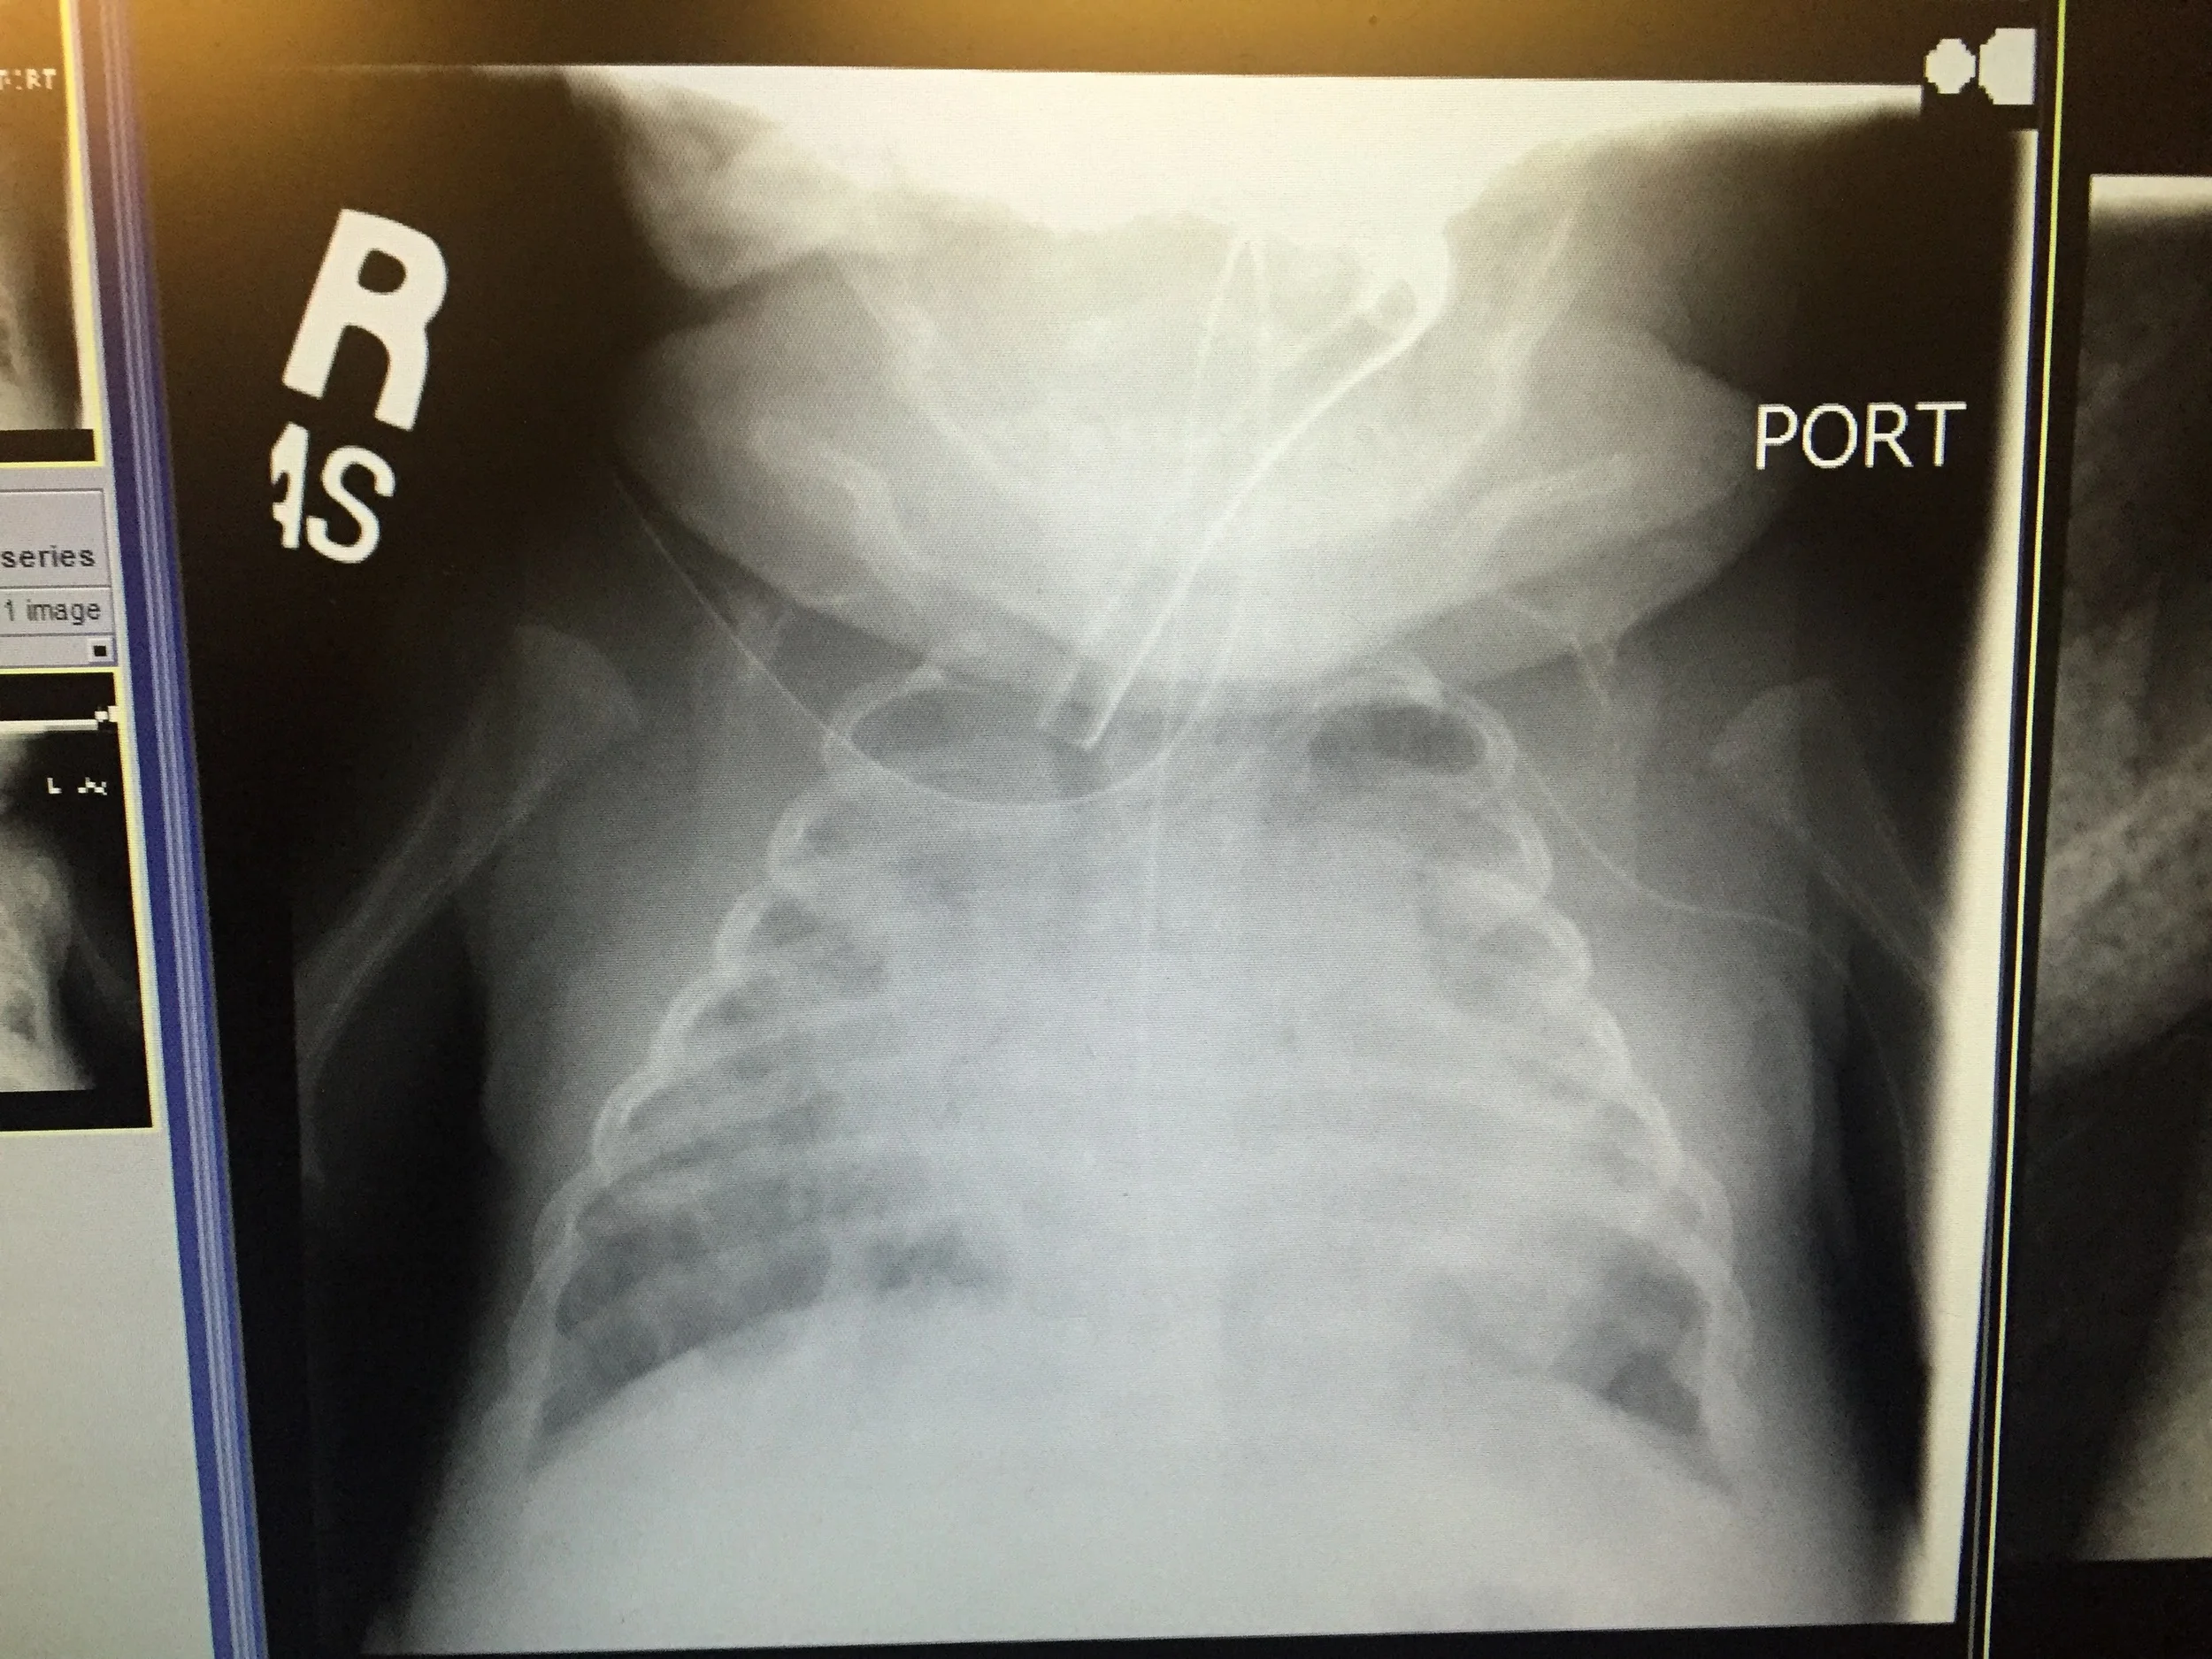

Her chest x-ray still shows haziness, which could indicate pulmonary effusion, pulmonary edema, or pneumonia.

Lana had another ECHO done yesterday, and her pulmonary pressures seem to have declined significantly. We're hoping that this is another small victory she can hang on to. Her chest X-ray is still hazy, but it's actually a small improvement from the prior x-ray.

They will also be doing another ECHO on her in a few days. She has a moderately sized PDA that they are concerned about. It's basically a hole in their heart that allows a portion of the oxygenated blood from the left heart to flow back to the lungs by flowing from the aorta (which has higher pressure) to the pulmonary artery. If this shunt is substantial, Lana becomes short of breath and the additional fluid returning to the lungs increases lung pressure to the point that she has greater difficulty inflating the lungs (see image below). This hole usually closes upon birth for most babies, but sometimes they don't. If it gets worse then they will have to perform surgery on her.